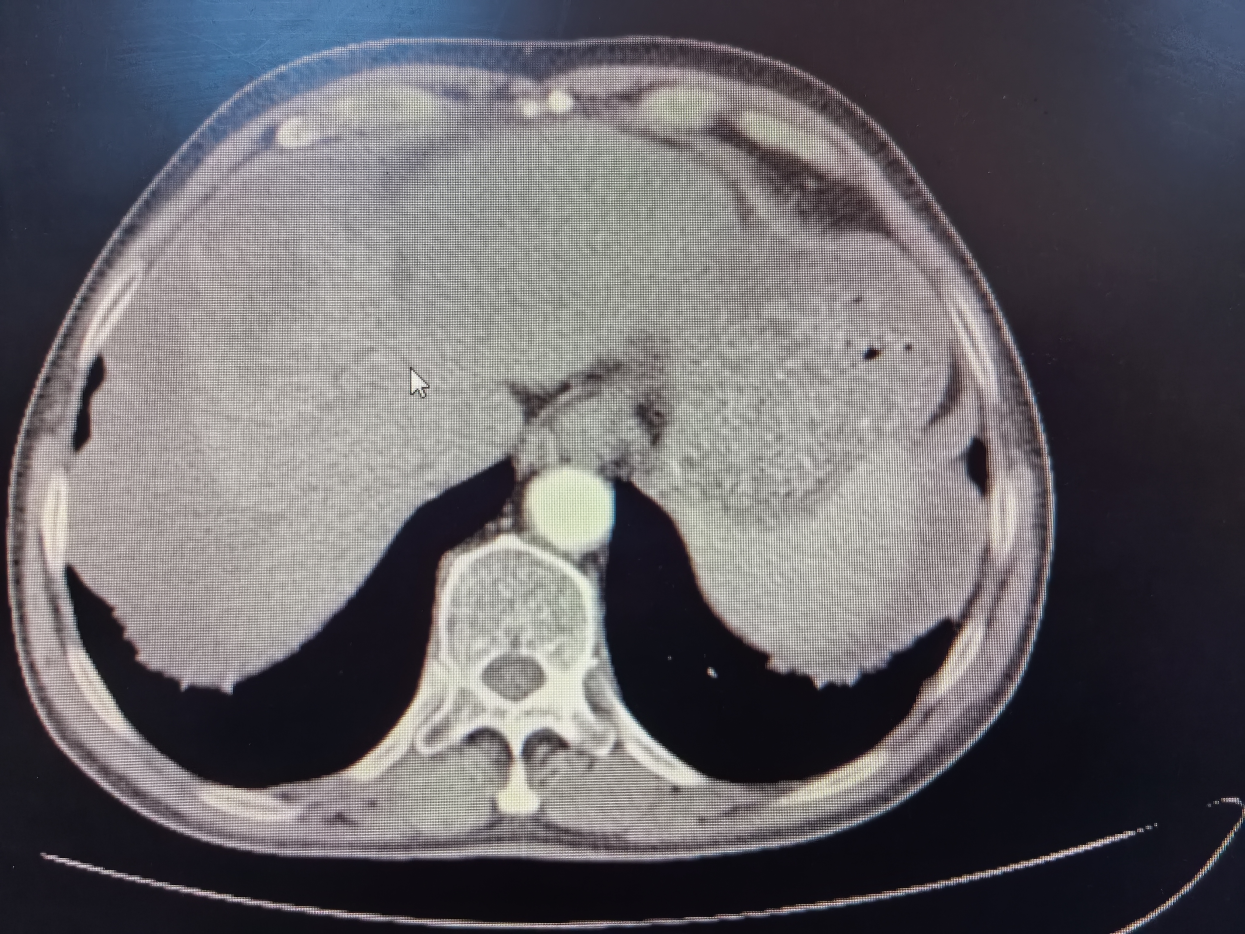

介入治療由肝膽外科劉楊波副主任醫(yī)師主刀,通過(guò)精準(zhǔn)的血管置管定位,采用化療藥物對(duì)腫瘤進(jìn)行局部灌注治療。經(jīng)過(guò)兩個(gè)周期的介入治療,規(guī)律口服靶向藥后,候先生的腫瘤體積明顯縮小,由原來(lái)的9.0cm縮小至7.0cm,腫瘤邊界清晰,無(wú)大血管侵犯,周邊子灶已無(wú)活性,達(dá)到了預(yù)期的治療效果,成功由臨床不可切除肝癌轉(zhuǎn)化可切除肝癌?;颊咴偃朐汉?,肝膽外科手術(shù)團(tuán)隊(duì)隨即為候先生制定了詳細(xì)的肝切除手術(shù)方案。手術(shù)當(dāng)天,蔣水平博士和劉楊波、薛文副主任醫(yī)師組成的手術(shù)團(tuán)隊(duì)成功在腹腔鏡下切除了患者體內(nèi)的肝臟腫瘤。術(shù)后,候先生恢復(fù)良好,影像檢查提示局部未見(jiàn)腫瘤和轉(zhuǎn)移征象,腫瘤指標(biāo)恢復(fù)正常,標(biāo)志著手術(shù)取得了圓滿成功。

術(shù)前 CT